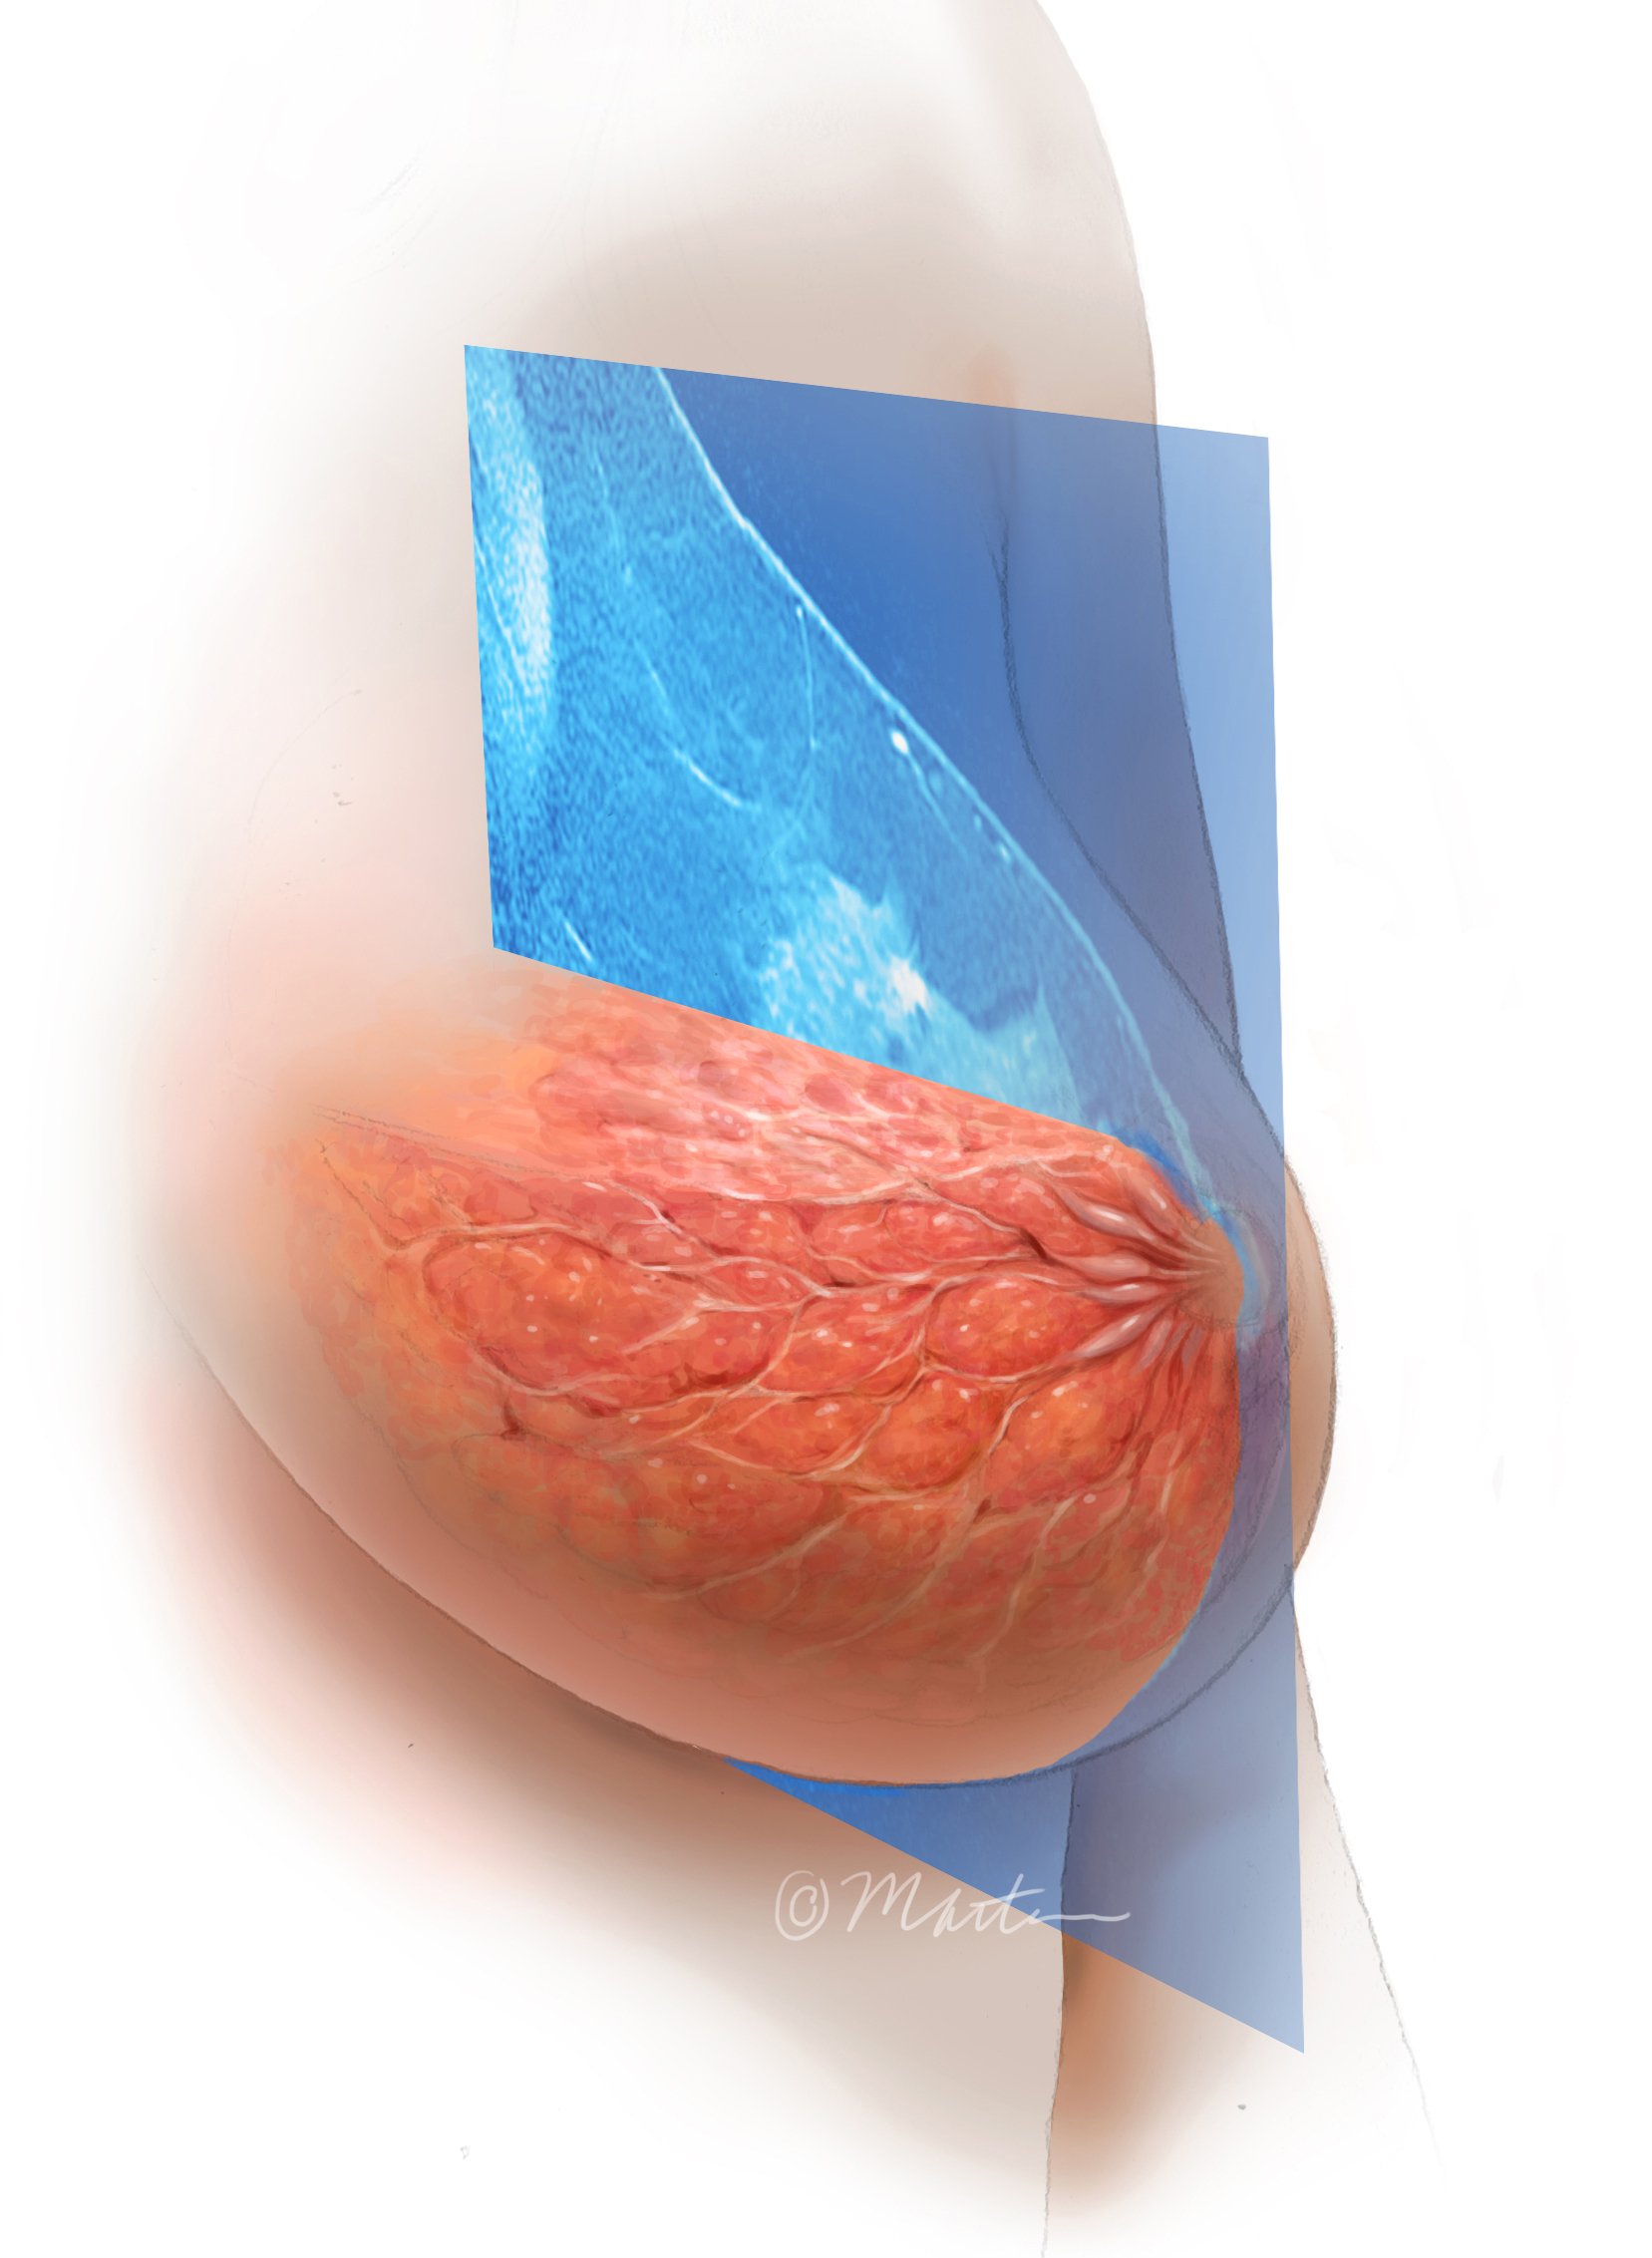

Breast MRI